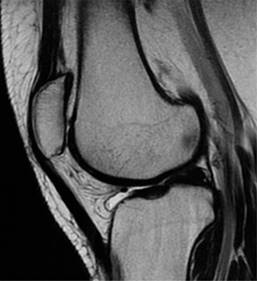

La duplicación patelar es una entidad infrecuente, donde se desarrollan una patela y una patela accesoria a partir de dos núcleos de osificación (Figuras 2 y 3).

Figura 2: Resonancia magnética de rodilla izquierda en secuencia T2 sagital, en la que se ve la patela en adecuada situación.